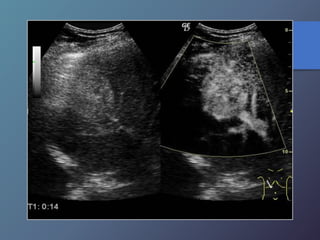

• Variable desde mas hipoecoicas hasta complejas o

Hiperecogénicas.

• Los chc pequeños son hipoecoicos, con halo periférico

fino que Corresponde a la capsula.

• Los chc de mayor diámetro, tienden a ser Heterogéneas,

complejas.

• Son hipervasculares, con vasos dismórficos.

Características Ecográficas

Ca hepatocelular con hemorragia